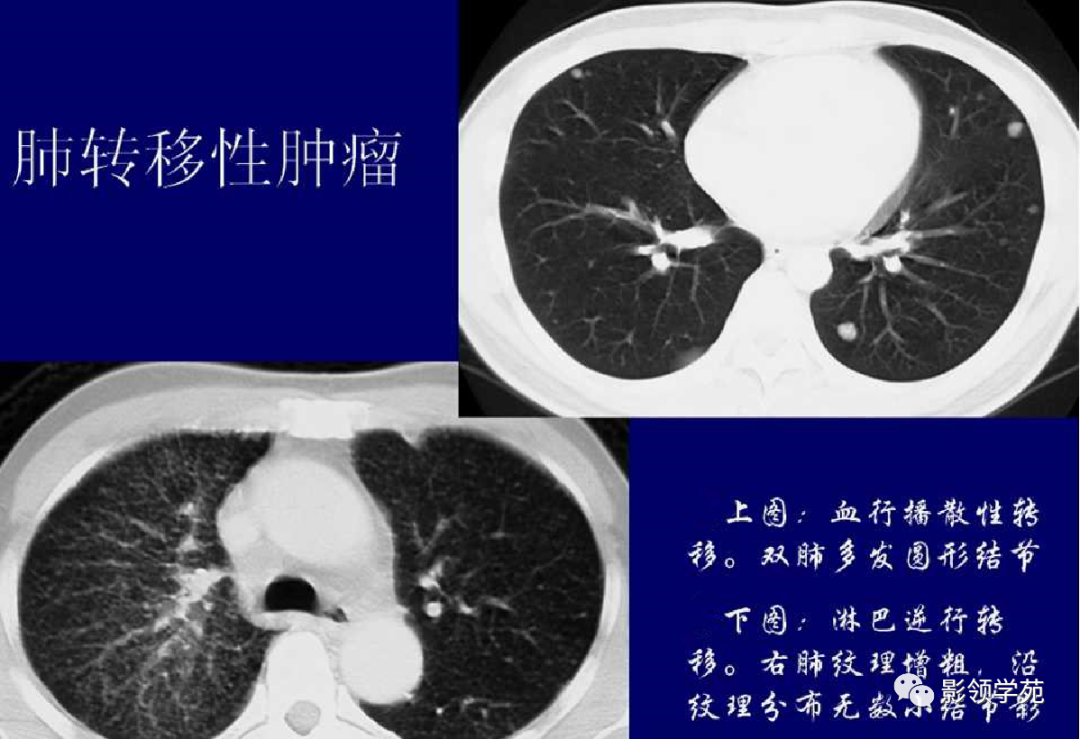

1. 血行性转移 :多发或单发结节,大小不一,边缘较清楚。少数结节伴出血时出现晕轮征,即有略高密度影像环绕结节,使病变边缘模糊。病变有钙化常见于骨肉瘤或软骨肉瘤转移。转移瘤亦可表现为空洞。两肺多发的小结节影具有随机分布的特点,HRCT显示结节位于小叶中心、小叶间隔、支气管血管束及胸膜,结节大小不均匀。

2.淋巴道转移:HRCT表现为沿淋巴管分布的结节。支气管血管束结节状增粗,并有结节,小叶间隔呈串珠状改变或增粗,小叶中心有结节灶,并有胸膜下结节。病变在两肺弥漫分布或局限于某一部位,以中下肺多见。常合并胸腔积液。约半数病人有纵隔及肺门淋巴结肿大。